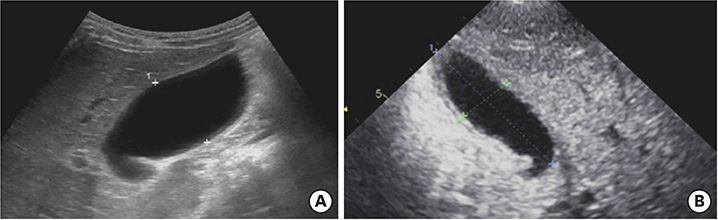

On the first day after admission, he received 2 g/kg IVIG and 50 mg/kg/day aspirin, following which his fever subsided and no further IVIG treatment was needed. His first echocardiography showed myocarditis (ejection fraction [EF], 45%) and mild ectasia of left main coronary artery (3.2–3.4 mm in diameter). On the second day after his admission, echocardiography (second follow-up) showed improved mild myocarditis (EF, 55%), improved ectasia of left main coronary artery (2.7–2.8 mm in diameter), and severe GB distension (8.9×4.6 cm in size), which possibly indicated GB hydrops (Fig. 2A). On the fourth day after his admission, although he had no fever and exhibited improvements in KD symptoms (i.e., eye injection, rash on abdomen, and cervical lymphadenopathy), he still complained of abdominal pain, distension, and tenderness of the RUQ. Follow-up laboratory findings were improved: neutrophilic leukocytosis (6,130 cells/mm3, with 33% neutrophils); decreased CRP (4.4 mg/dL), BNP (347 pg/mL), AST (40 U/L), and ALT (72 U/L); and improved hyperbilirubinemia (total bilirubin, 0.7 mg/dL). Echocardiography (third follow-up) showed normal completely improved carditis and still severe GB distension (10.2×5.5 cm in size) (Fig. 2B). Abdominal ultrasonography (US) was performed, which showed a markedly distended GB without stone, sludge, or wall thickening as well as normal bile ducts and liver morphology, which confirmed GB hydrops (Fig. 3A). On the sixth day after his admission, although his signs of KD had nearly disappeared, he still complained of abdominal discomfort, which had been moderately improving. The second follow-up abdominal US revealed a no notable change in GB distension compared to previous sonographic findings (Fig. 3B). An abdominal computed tomography (CT) scan was also obtained to exclude other hepatobiliary abnormalities, which showed similar findings as sonography, including a marked dilatation of the GB (8.0×5.5 cm in size) without stone, sludge, or wall thickening as well as normal bile ducts and liver morphology (Fig. 4). No complications necessitating surgical intervention had occurred and he was discharged 7 days after admission with only mild tenderness on the right upper-mid quadrant.

Fig. 3

Abdominal ultrasonography showed severe gallbladder distension (A) 9.8×4.9 cm in size and (B) 9.3×4.3 cm in size.

After discharge and 23 days of fever onset, a follow-up abdominal sonography revealed a slower regression of the GB hydrops (Fig. 5A). Echocardiography performed at 81 days after onset of fever revealed complete improvement of both the coronary artery lesion and GB hydrops (Fig. 5B).

Fig. 5

Abdominal ultrasonography (A) performed at 23 days after fever onset revealed a slow regression of the gallbladder hydrops (6.7×3.2 cm in size). Echocardiography (B) performed at 81 days after fever onset revealed a complete improvement in gallbladder hydrops and a normal gallbladder.